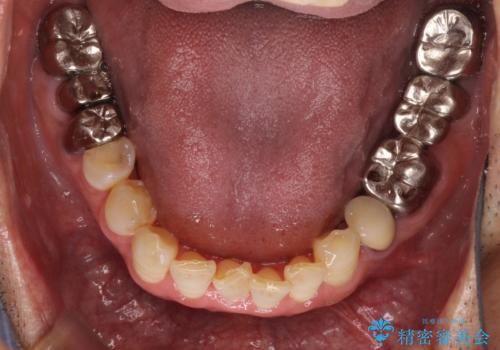

- 奥歯に違和感を感じており、抜歯の必要性を感じて来院された患者様です。

診査の結果、5本の奥歯を抜歯してインプラントによる補綴治療が必要と診断されました。

患者様が違和感を感じていない左下の奥歯の治療は今回は見送り、それ以外の治療が必要な奥歯を治療することとしました。